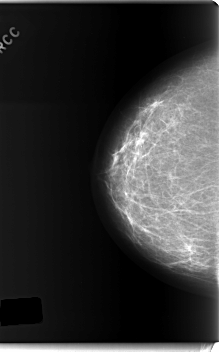

C_0187_1.RIGHT_CC

RIGHT_CC LINES 5968 PIXELS_PER_LINE 3720 BITS_PER_PIXEL 12 RESOLUTION 50 NON_OVERLAY